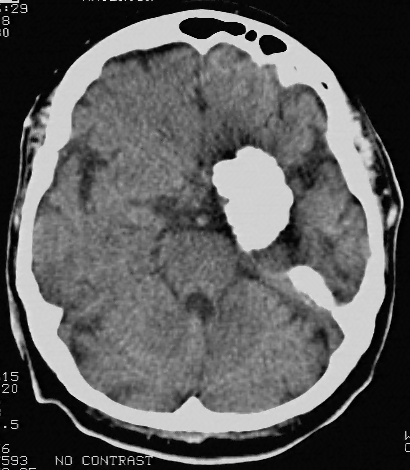

Sample results of visualization, registration and segmentation

of volumetric pathological neuroimages

This picture demonstrates the results of several sample techniques our

team is developing for achieving the goal of classification-driven

semantic based neuroimage indexing and retrieval. Top left: 3D lesion

visualization (hemorrhage on CT ). Top right: multi-modality

deformable image registration between a digital brain atlas (normal on

MR T1) and a volumetric pathology image (tumor on MR T2). Bottom:

automatic lesion detection and segmentation (bland infarct on CT).